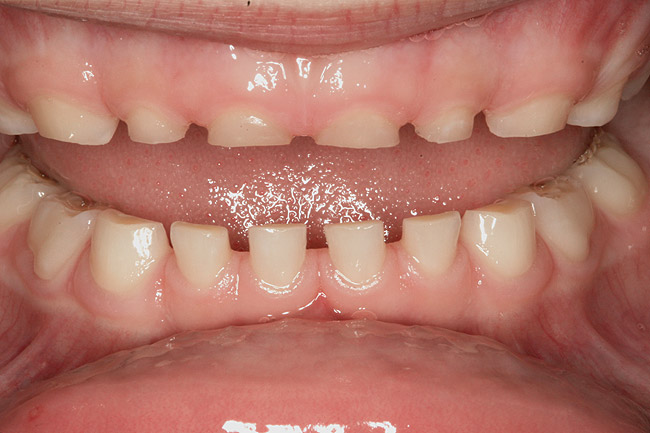

(14.) Angle Class III occlusion with constricted maxilla.

Figure 14

(15.) Cephalometric evaluation demonstrates significant tonsillar blockage of the airway and bimaxillary retursion.

Figure 15